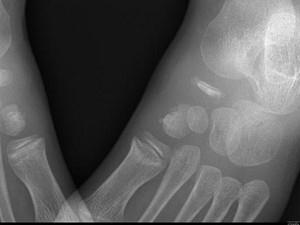

问题 男,5岁,足背肿痛,请结合图像,选出最可能的诊断 ( )

选项 A、软骨发育不全 B、剥脱性骨软骨炎 C、跗舟骨骨折 D、成骨不全 E、跗舟骨缺血坏死

答案 E